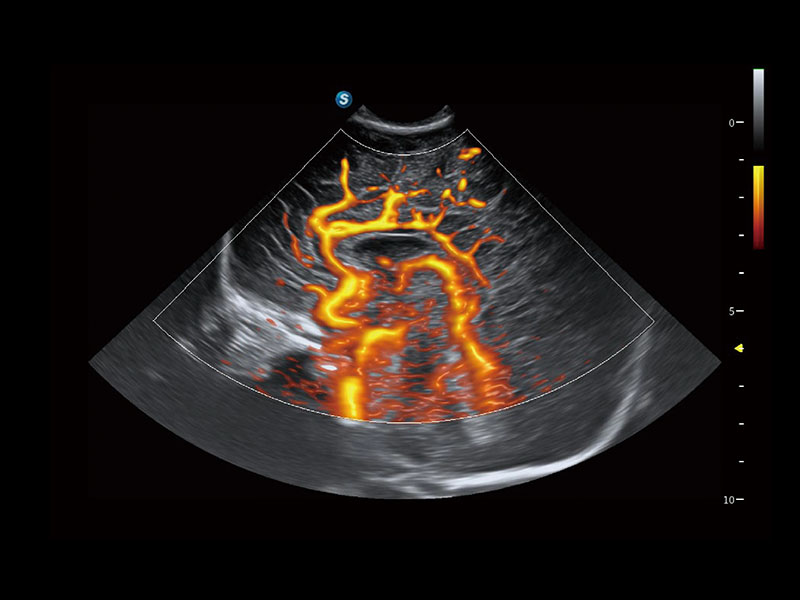

便携式彩色多普勒超声诊断系统

作为开立医疗全新打造的高端全域笔记本超声,X11集成了当前先进的硬件架构和精密的设计工艺,提升多科室临床医生在常规影像检查中的诊断能力,为临床提供全面的诊疗支持。